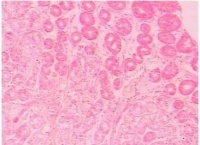

所谓胃窦炎antral gastritis,antrum gastrititis是指局限于胃窦部的一种慢性炎症,主要病变多局限于黏膜层,但也漫延至肌层或浆膜层。在病变部分出现水肿、炎症细胞侵润和纤维组织增生,使局部变厚,甚至狭窄;部分病例可有黏膜表面糜烂、肠腺上皮化发生变化。

胃窦炎好发于30岁以上的男性,表现为上腹部饱胀,隐痛或剧痛,常呈周期性发作,可伴有嗳气、反酸、呕吐、纳差、消瘦等,慢性胃窦炎还可表现为厌食,持续性腹痛,失血性贫血等。胃窦炎病变多局限于粘膜肌层,亦可蔓延至肌层和浆膜层。胃窦粘膜表现为水肿、充血,炎性细胞浸润和纤维组织增生,其中以粘膜下层最为明显。

胃可分为四个部分:贲门部、胃底部、胃体部和胃窦部。胃的入口为贲门,出口为幽门。胃窦指的是幽门与胃角切迹平面之间的部分。胃窦炎好发于30岁以上的男性,表现为上腹部饱胀,隐痛或剧痛,常呈周期性发作,可伴有嗳气、反酸、呕吐、纳差、消瘦等,慢性胃窦炎还可表现为厌食,持续性腹痛,失血性贫血等。胃窦炎病变多局限于粘膜肌层,亦可蔓延至肌层和浆膜层。胃窦粘膜表现为水肿、充血,炎性细胞浸润和纤维组织增生,其中以粘膜下层最为明显。此外,当有粘膜糜烂,腺体萎缩与肠腺增生,胃窦炎很少单独存在,常与消化性溃疡或胃癌同时存在,因为胃窦炎与萎缩性胃炎、胃溃疡、胃癌关系密切,应引起我们的高度重视。

胃窦炎是发生于胃窦部的慢性炎症,一般可分为浅表性和萎缩性两类。通过多年来的观察研究,发现胃癌与萎缩性胃窦

炎之间有着密切的关系。不少学者报道萎缩性胃炎病人的癌变率约为10%,萎缩性胃窦炎癌变的危险性大于正常人20倍,在我国,从胃癌高、低发区的调查中发现,萎缩性胃炎的发病率在胃癌高发区明显增高。对于萎缩性胃窦炎演变成胃癌的机理,一般认为萎缩性胃炎时,胃黏膜功能和结构都发生异常改变,胃液游离酸减少,PH升高,胃内细菌量增加,特别是在硝酸盐还愿酶阳性菌存在的情况下,硝基(NO3-)被还原为亚硝基(NO2-),而使胃液亚硝基(NO2-)含量升高,给胃内合成亚硝基化合物提供了致癌的必要条件,但要萎缩到何种程度,需要多少时间才会癌变,尚不明了。一般说来,胃黏膜活检时伴有重度肠腺上皮化生和间变者,更易癌变。